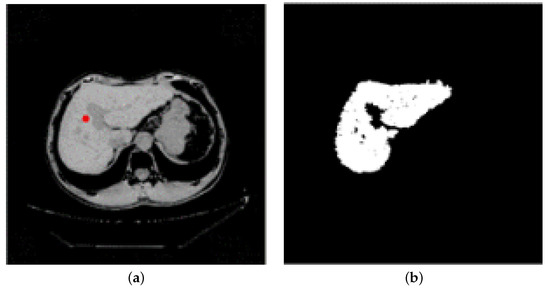

There are artifacts, noise, text information, and other adverse factors in abdominal CT images. Bones, spine, and other organs and tissues whose gray values are similar to those of liver will also affect the segmentation effect. In order to improve the accuracy of segmentation, this paper preprocesses the abdominal CT image: firstly, the image contrast is enhanced by brightness mapping function to reduce the influence of organs and tissues with similar gray values on segmentation. We map the brightness in the gray image to the new value and make 1% of the data have low intensity, high intensity, and saturation. Then, the median filter of 3 × 3 is used to denoise and smooth the image, so as to effectively reduce the artifacts and noise in abdominal CT images, and make the contour of the liver clearer to a certain extent. Finally, we select the threshold according to the distribution of the gray value of the abdominal CT image for threshold segmentation, thus we can remove the parts whose gray value is significantly higher than that of the liver area, such as bone, spine, and text information, and increase the accuracy of the segmented liver image. The T value is set as the threshold. When the gray value is greater than T, we can remove it as spine, rib, and skin, and remove the residual information of the median filter at the same time. When the gray value is between 0 and T, we keep it. The preprocessing process is shown in Figure 2.

Figure 2.

Preprocessing: (a) The original image. (b) The image after contrast enhancement. (c) The image after median filtering. (d) The image after bone and text removal.